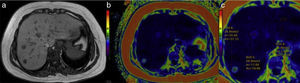

There are other techniques for evaluating parenchymal iron. Among them, the so-called MRI R2 and R2* technique can provide parametric images that reflect the iron content in the liver and spleen (Figure 9). The results of comparisons with liver biopsy have been dissimilar due to the heterogeneity of the iron deposits. They are generally similar, but MR has the obvious advantages in treatment follow-up and patient preference because of its noninvasiveness.42,43

Hemochromatosis. a) In the colorimetric map, the reds correspond to the higher part of the scale, indicating greater iron concentration in the liver parenchyma. b) Also note the red dot in the amplified image of the spleen produced by the Gamna-Gandy siderotic bodies. c) In addition, the anatomic image in T1 of this patient showed decay of the parenchymal signal of the pancreas (arrow) and the presence of enlarged peripancreatic lymph nodes (arrows) in relation to the hemochromatosis (d).

With the technique described by Gandon et al., values of 40 to 100¿ml/ml represent a slight iron overload in liver tissue, whereas values of 100 to 200¿ml/ml correspond to moderate overload, and those over 300¿ml/ml indicate major overload, which can saturate the sequences and falsify the readings.41 The MRI R2-R2* measures the parenchymal iron concentration in mg of Fe/g.42,43